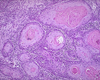

What is this?

Salpingitis